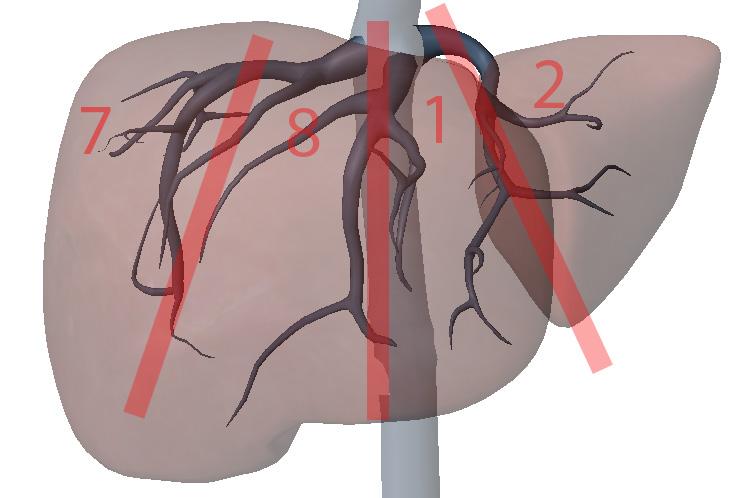

What are the hepatic veins key to?

division of the liver longitudinally

What are the portal veins key to?

transverse division of the liver

What is section 1?

Left Medial superior

What is section 2?

Left lateral superior

What is section 3?

Left lateral inferior

What is section 4?

Left medial inferior

What is section 5?

Right anterior inferior

What is section 6?

Right posterior inferior

What is section 7?

Right posterior superior

What is section 8?

Right anterior superior